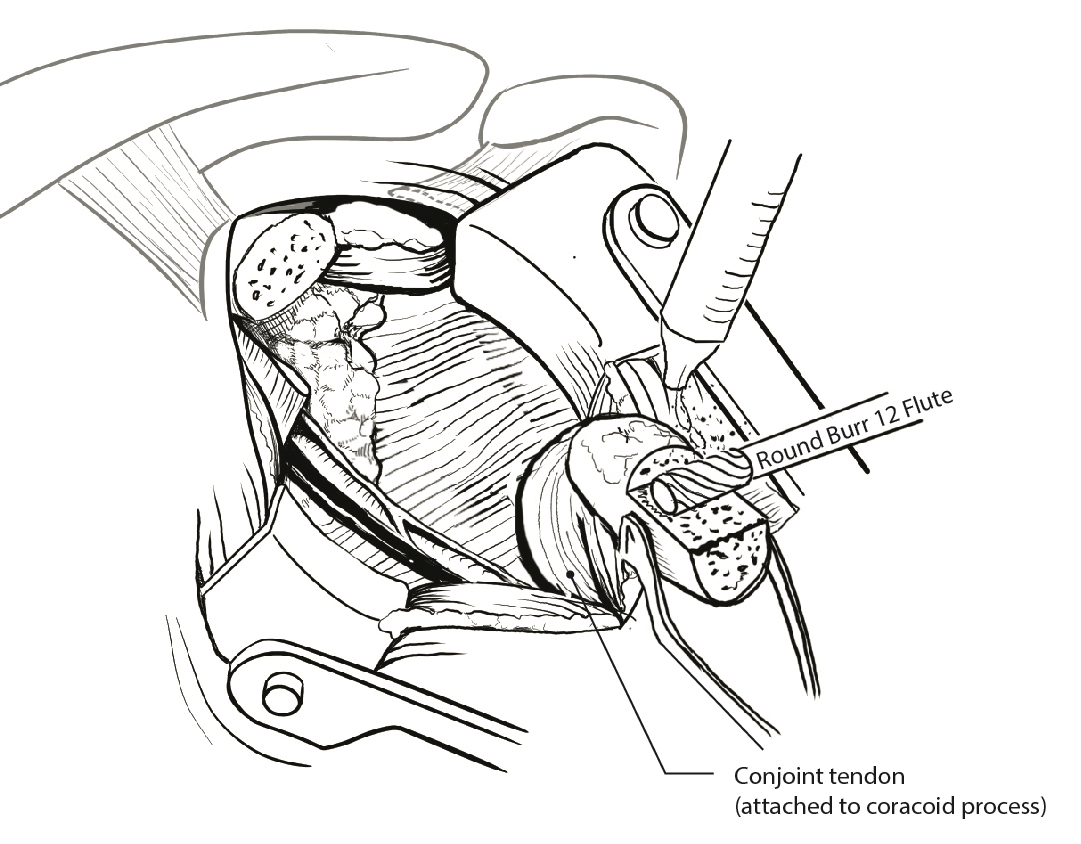

Secure coracoid

- inferior half of glenoid

- no medial overhang

- secure with 2 x bicortical screws with compression

Bone block positioning

Concepts

- coracoid must not overhang medial to avoid osteoarthritis

- coracoid < 5 mm medial to glenoid rim

- coracoid lower half of glenoid 2 - 5 o'clock

- fixation screws purchases posterior glenoid cortex

- screws do not penetrate articular surface